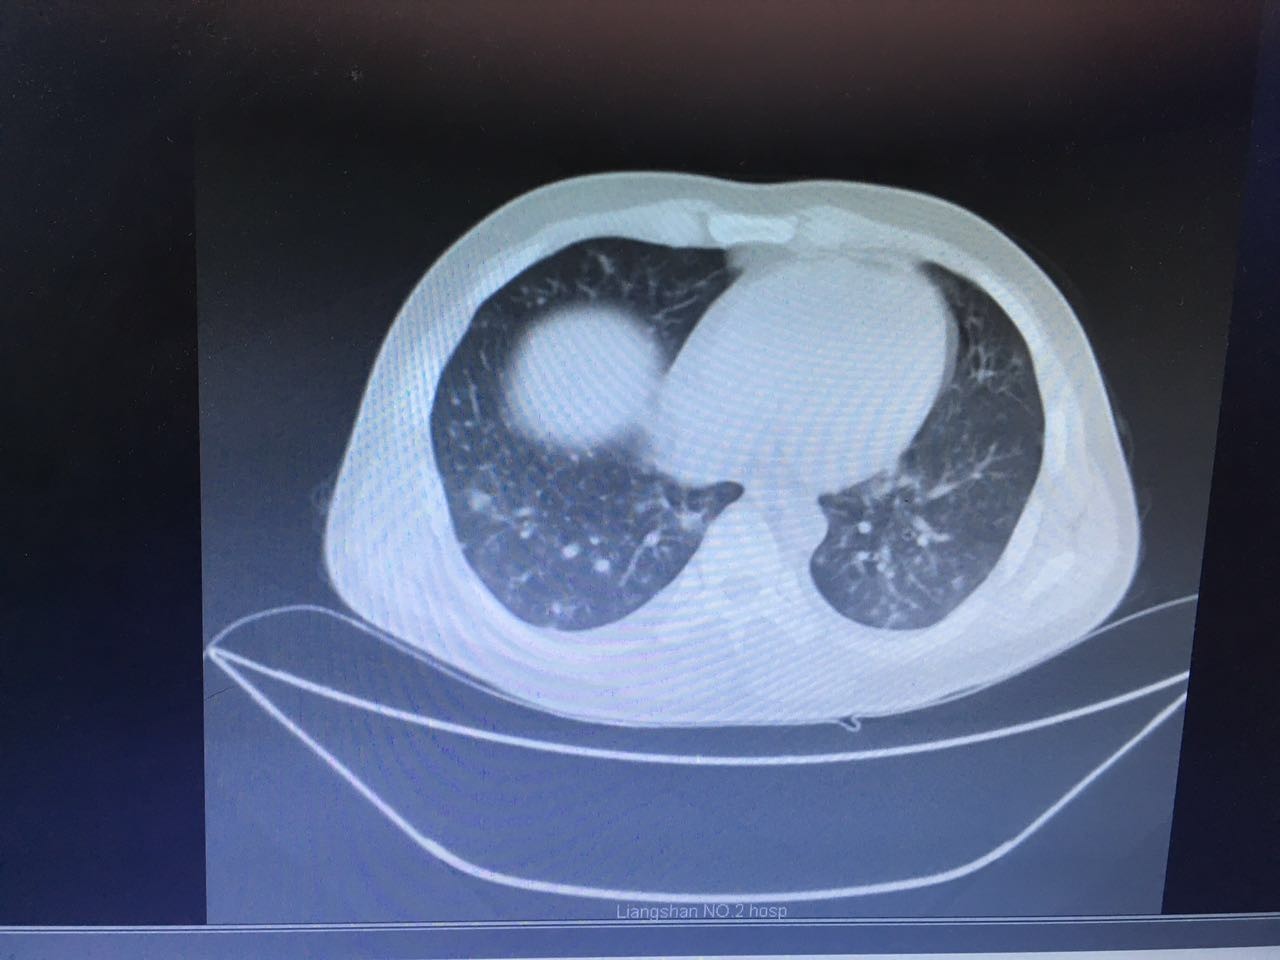

第二天,肺部CT做下来,我们傻了,和胸片差别太大了!从中下肺开始,那是大片的阴影啊!CT提示为间质性肺炎,找放射科主任读片,认为不符合肺结核、肺癌的表现(图1-3.)马上再回到病床前再次确认——没有吸烟史、没有慢性咳嗽史、没有咯血、没有盗汗史。再查体:浅表淋巴结确实不肿大,双肺呼吸音可以算略粗糙也可以算清晰。——这么这么静默的肺部体征,这么这么差的影像学结果,马上补查肿瘤标志物和自身免疫全套吧!

图2